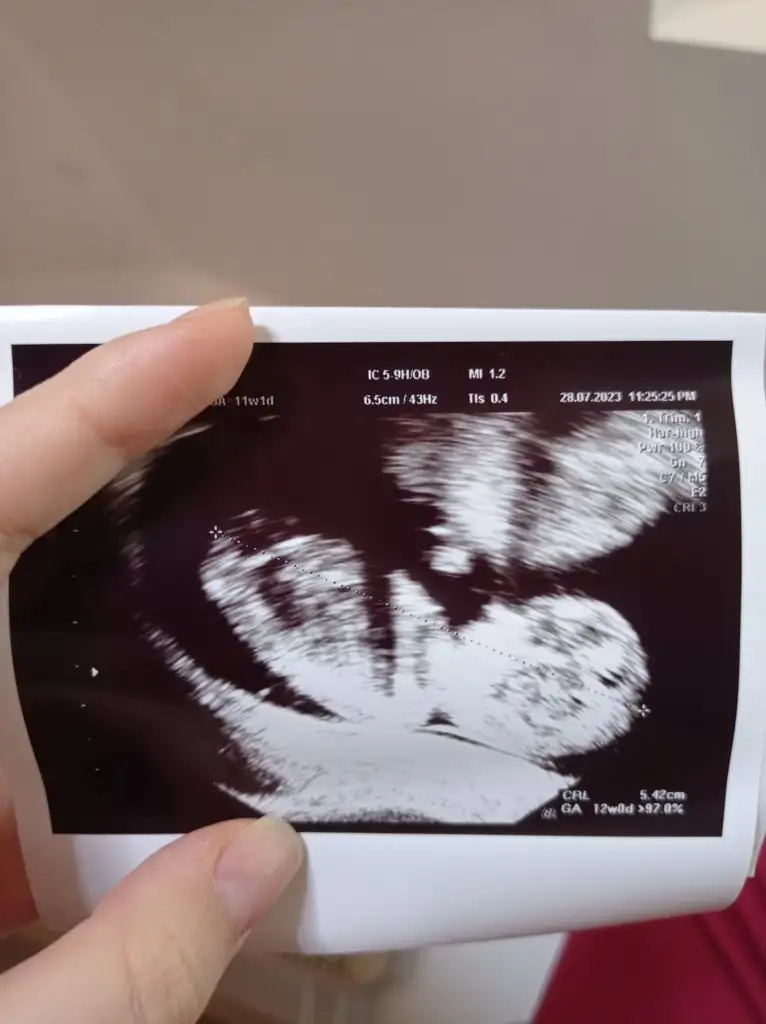

Ay ben hiç anlamıyorum canım ya,Kızlar selam bugün kontrolüm vardı 12 haftalığım, Dr herşey yolunda haftasina uygun gayet güzel gelişiyor dedi ikili test icin kan verdim Dr kendisi baktı ultrasonda ense kalınlığı güzel normal dedi, cinsiyet tahmini hiç yapmadı, sizin aranızda nub falan anlayan varsa bakabilir mi acaba